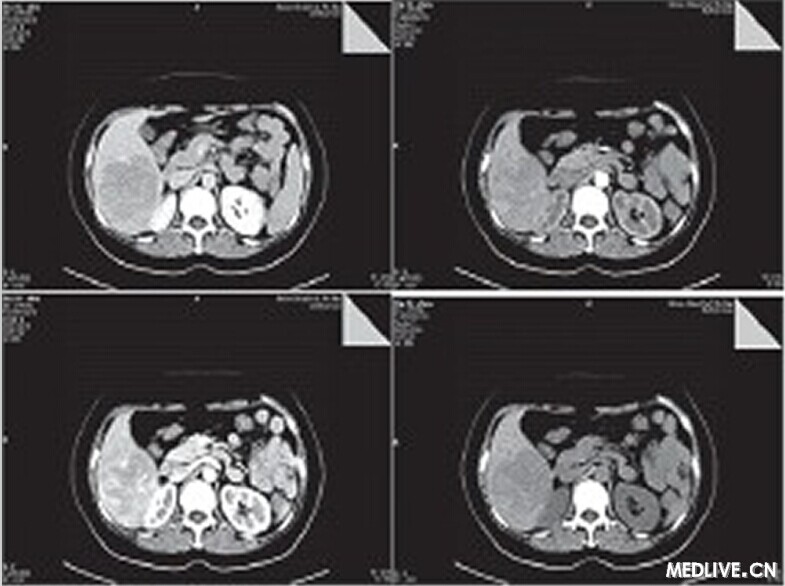

• 【PHILIPS每日一例】【誤診分析】肝臟血管平滑肌脂肪瘤誤診為肝癌一例

【PHILIPS每日一例】【誤診分析】肝臟血管平滑肌脂肪瘤誤診為肝癌一例

患者,女,50歲,農民。

因右上腹疼痛1月余,外院B超診斷為肝癌入我院治療。既往無肝炎病史,無飲酒史,無遺傳病史,無高血壓糖尿病史。

體檢:神志清楚,正力體型,皮膚鞏膜無黃染;心肺聽診未見異常;腹軟,肝脾肋下未及,腹水征陰性,雙下肢無水腫。

入院后輔助檢查:甲胎蛋白正常,肝功能正常,血常規正常,便常規見膿球1~3個,HBV和HCV相關病原學檢查陰性。

CT檢